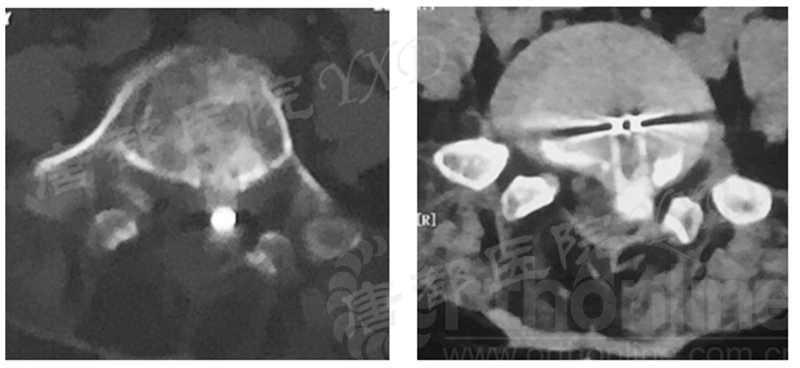

影像学检查:

诊断:腰椎间盘突出症术后复发

手术方案:显微镜辅助MI-TLIF腰椎翻修术

术中视频:http://api.orthonline.com.cn/attach/Case2.mp4(术中发现因前三次侧路及后路内镜手术的操作,术区大量瘢痕组织增生、与神经粘连严重;此外,摘除头侧游离髓核时连接有软骨终板脱落;在显微镜操作下,安全地将神经进行充分松解,压迫神经的游离髓核及软骨终板彻底清除。无手术并发症)